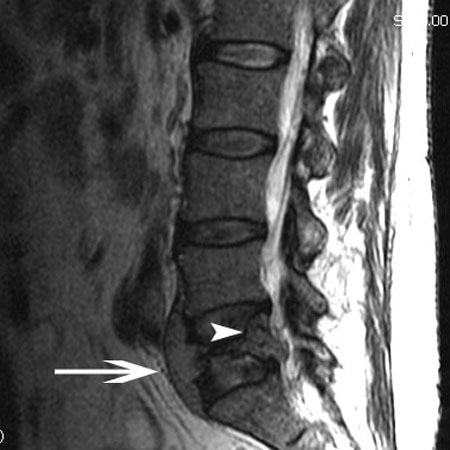

ლიმფომის მაგნიტური-რეზონანსული ტომოგრაფია: ისრის წვერი მიუთითებს რბილქსოვილოვან წარმონაქმნზე, რომელიც იჭრება ხერხემლის არხში. ისარი მიუთითებს სიმსივნეზე, პროტრუზიით L5 მალის სხეულის წინ

ექიმ Dr K. Singh საკუთრება; გამოყენებულია ნებართვით